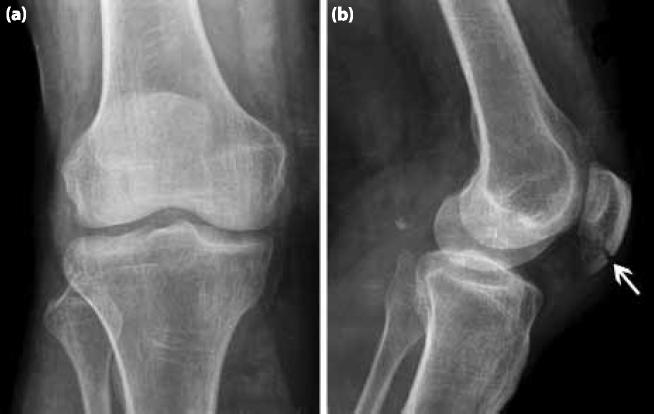

Ultrasonographic Examination of Patella.